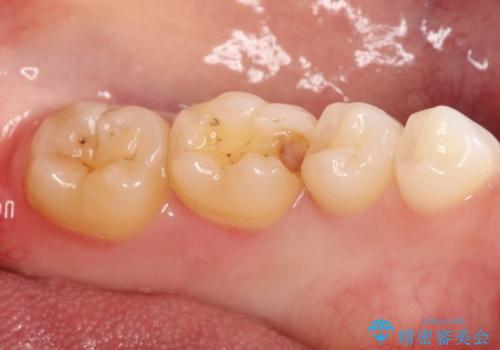

- 金属の詰め物がはずれてしまったので、精度の良いセラミックをいれたいのとのこと来院されました。

セラミックインレーにて治療することとなりました。

拡大鏡を使用して精度の高いインレーを装着しました。